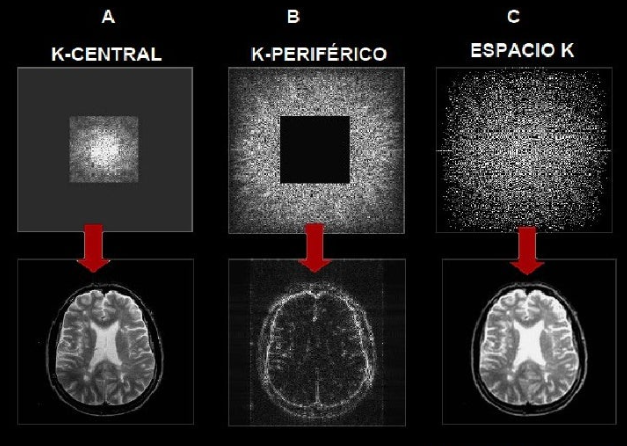

Descubra como a "receita" da imagem de RM é montada e a diferença entre contraste e resolução.